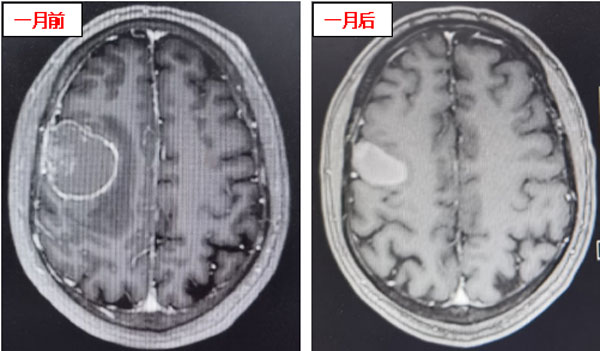

该患者为一名52岁男性,在2年前因发现右肺上叶大细胞神经内分泌癌接受手术治疗。近日,他在日常活动中突发癫痫、意识丧失而跌倒。头颅核磁显示:右额顶叶转移瘤伴瘤卒中及瘤周水肿。患者头痛明显,癫痫时有发作,左侧肢体肌力仅为3级。经过我院内科治疗后,患者头痛有所减轻,但肌力未见恢复,频繁出现口角及肢体抽搐。

患者在接受3次射波刀治疗后,头痛症状明显减轻,癫痫症状消失,肢体肌力明显好转。接受治疗1个月后,患者肢体肌力恢复正常,未再出现口角、肢体抽搐及头痛、头晕等症状,仅左侧手指尖偶有麻木感。复查头颅核磁显示:颅内病灶明显缩小,周围无明显水肿坏死征象,安全性良好,这意味着射波刀治疗成功遏制了颅内转移瘤。